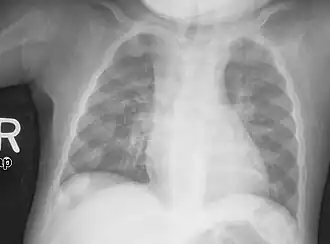

An X-ray or radiograph of an advanced patient with rickets tends to present in a classic way: the bowed legs (outward curve of long bones of the legs) and a deformed chest. Changes in the skull also occur, causing a distinctive "square-headed" appearance known as "caput quadratum".[18] These deformities persist into adult life if not treated. Long-term consequences include permanent curvatures or disfiguration of the long bones, and a curved back.[19]